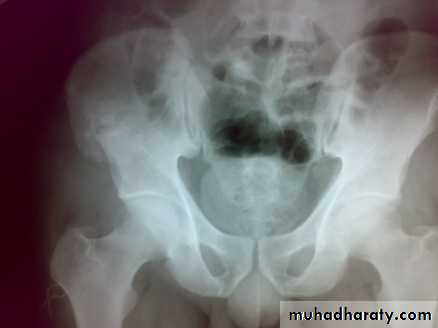

Unstable ring fractures

Caused by sever trauma.Extremely serious.

Carries high risk of visceral injuries.

There are fractures around or separation of symphysis pubis or sacroiliac joint.

Types of unstable fracture pelvic ring

1- antero-posterior compression (open book).

2- lateral compression (closed book).

3- Vertical force cause vertical displacement of the innominate bone on the same side.

4- combination injuries.